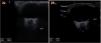

1a) Ecografía ocular de papila del nervio óptico (PNO) izquierdo el primer día de ingreso del paciente. La elevación/protrusión de 1,5mm de la papila supera los puntos de corte de 0,6mm propuestos ante sospecha de HTIC e incluso aquellos más exigentes de 1mm en HITC confirmada, así como los rangos revisados (0,6-1,2mm) para el papiledema2. 1b) Ecografía de control a los 5 días, tras inicio de tratamiento y mejoría clínica del paciente donde no se visualiza la protrusión de PNO.